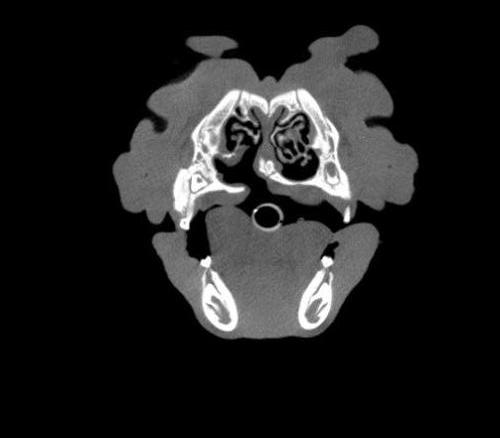

The Center now provides advanced imaging via cone beam CT. Cone beam CT is excellent for visualization of bony structures of the skull, nasal cavity, teeth, and ears. Cone beam CT is especially helpful for diagnosing dental disease and evaluation of jaw fractures. It can also be useful for evaluating the sinuses and tympanic bulla. Cone beam CT can be used in conjunction with nasal biopsy and culture to evaluate nasal discharge whether chronic or acute.